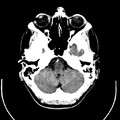

أشعة مقطعية للرأس توضح صورة المخ

Computed tomography of human brain, from base of the skull to top. Taken with intravenous contrast medium.